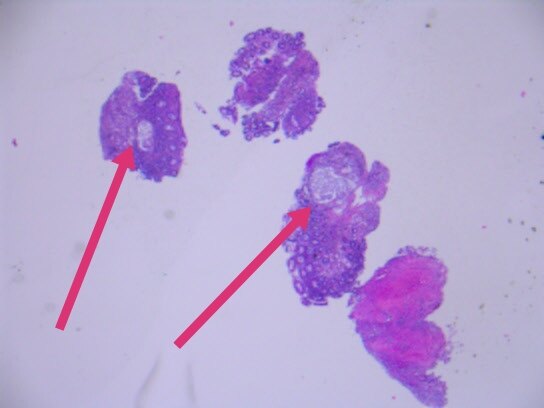

几天前,入我院行肠镜检查,并活检,显微镜下可见癌浸润于直肠粘膜之间。

最终,我们以上述HE形态为线索,老年男性,直肠占位,为XY坐标,我们初步音箱诊断就是前列腺腺泡腺癌浸润至前列腺腺外,累及直肠并形成肿块,浸润直肠全层至粘膜内。